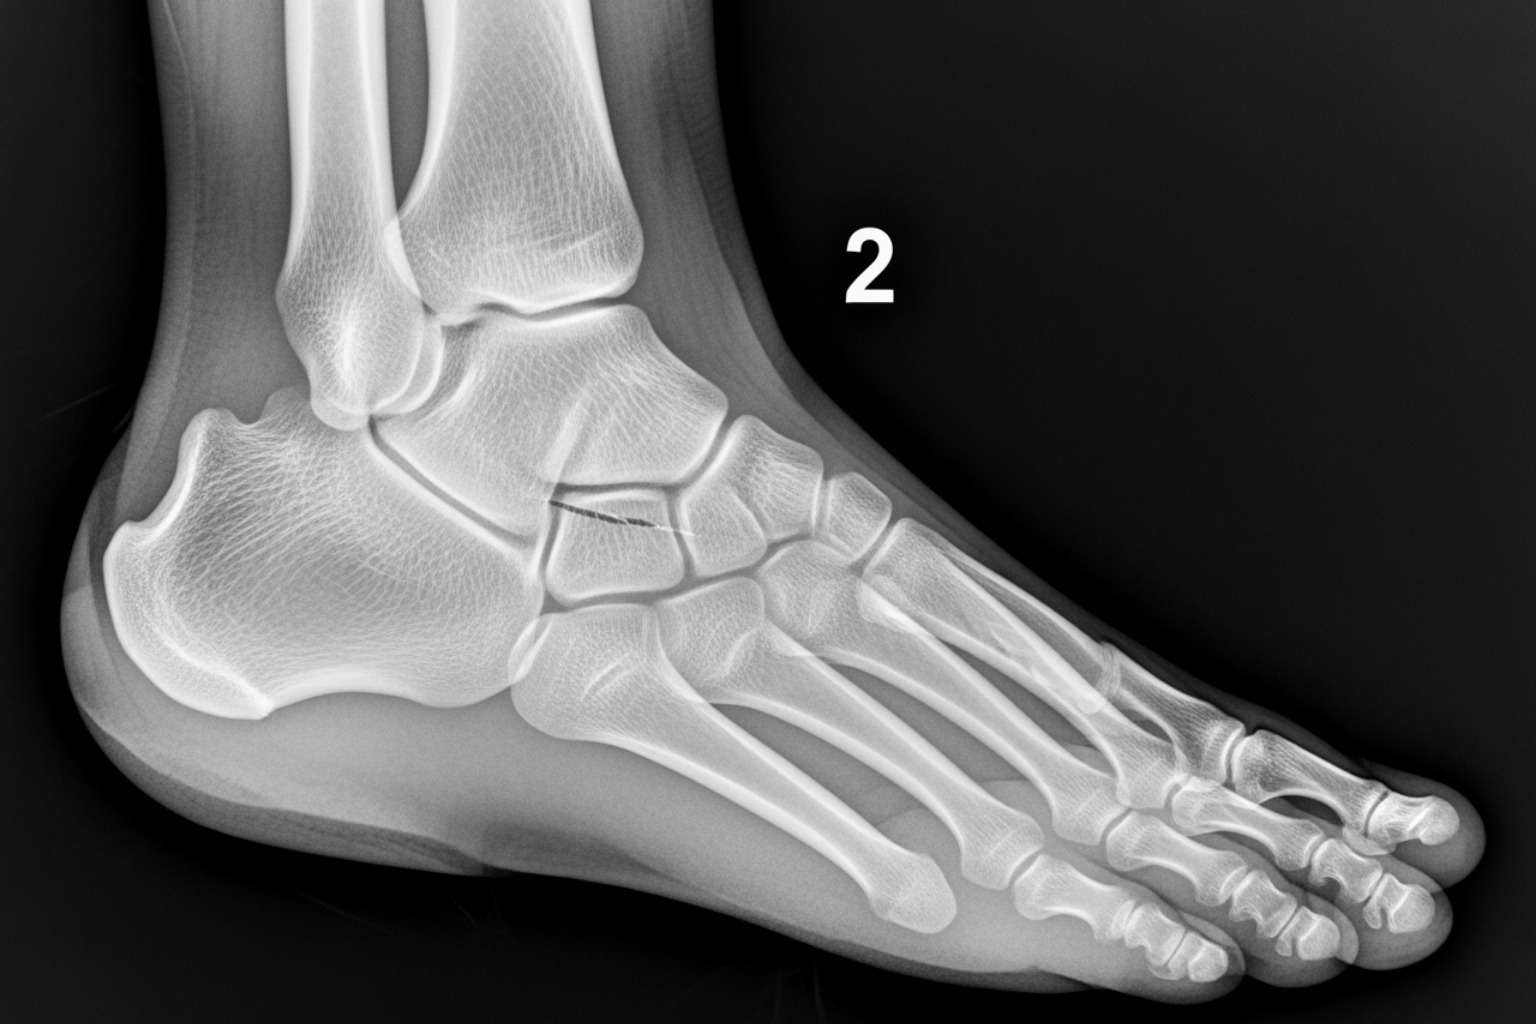

To see what's happening inside, your doctor might order imaging tests. X-rays are used to check for fractures or arthritis. If a soft tissue injury is suspected, an MRI or Ultrasound can provide detailed views of tendons, ligaments, and nerves to identify conditions like tendonitis or nerve entrapment.

Stress Fractures

Stress fractures are tiny, hairline cracks in bones, commonly the metatarsal bones, that develop from repeated force. This can result from the constant impact of running on hard surfaces, a sudden increase in activity, or starting a new high-impact sport. The pain usually starts slowly, worsens with activity, and improves with rest. You might also notice localized swelling, tenderness, and sometimes bruising.